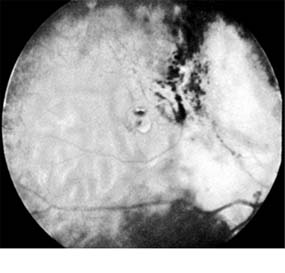

Retinoblastoma (Figure 10-32)

Retinoblastoma is a rare but life-endangering tumor of childhood. Two-thirds of cases appear before the end of the third year; rare cases have been reported at almost every age. Bilateral disease occurs in about 30% of cases. This is generally a sign of heritable disease, but up to one-third of heritable cases have purely unilateral disease. An allele within chromosomal band 13q14 controls both the heritable and nonheritable forms of the tumor. The normal retinoblastoma gene, present in every individual, is a suppressor gene or anti-oncogene. Individuals with the heritable form of the disease have one altered allele in every cell of the body; when the other allele in a developing retinal cell is affected by a spontaneous mutation, the tumor develops. In the nonheritable form of the disease, both alleles of the normal retinoblastoma gene in a developing retinal cell are inactivated by spontaneous mutation. Survivors of the heritable form of the disease (those 5% of new cases who had an affected parent or those who have had a germinal mutation) have almost a 50% chance of producing an affected child.

Figure 10-32

Figure 10-32: Retinoblastoma as viewed through the pupil.